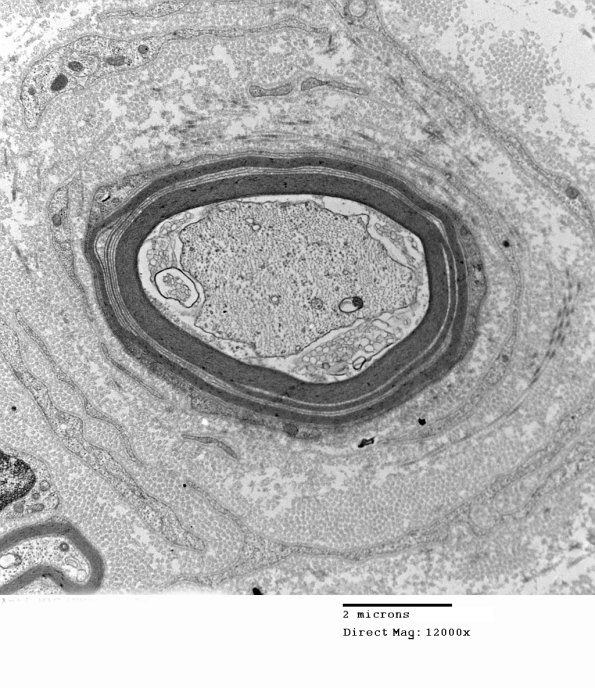

1E15A-D Multiple magnifications of WSM in a well preserved case. (electron micrographs)